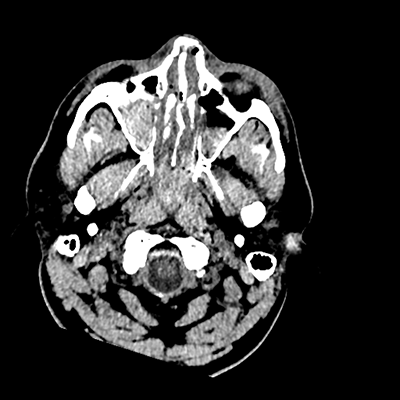

On day 5 of admission, he begins having intracranial hypertension again, spiking up to 40mmHg. You bolus with propofol and fentanyl, to no avail. You then push 30mL of 23.4% NaCl, which provides some brief improvement, allowing you to quickly get a non-contrast head CT. Unfortunately, he's now back up to 36mmHg. You review his labs, and note the following: Na 150, K 3.8, Cl 119, HCO3 18, BUN 21, Cr 0.85, glucose 136, sOsm 320.

NCHCT

NCHCT 5/20 5/20

NCHCT 6/20 6/20